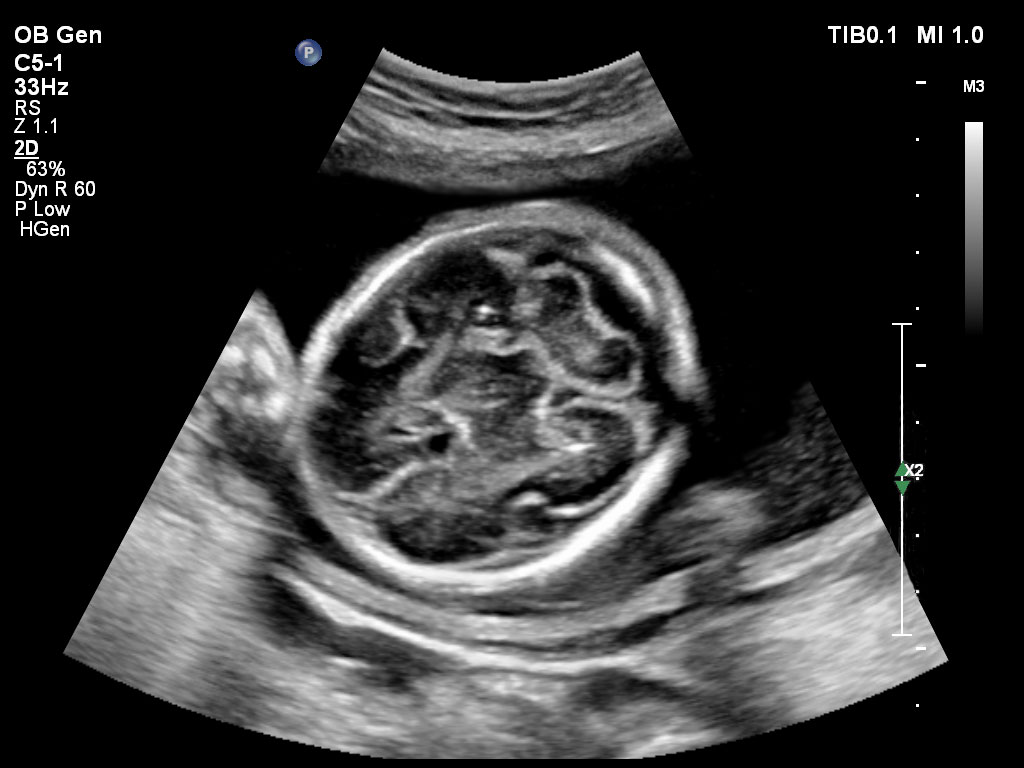

• C5-1 PureWave-Breitband-Convex-Schallkopf für hohe Eindringtiefen in der Gynäkologie und der Geburtshilfe, für Patientinnen mit Schwangerschaftsdiabetes oder vorzeitigem Blasensprung